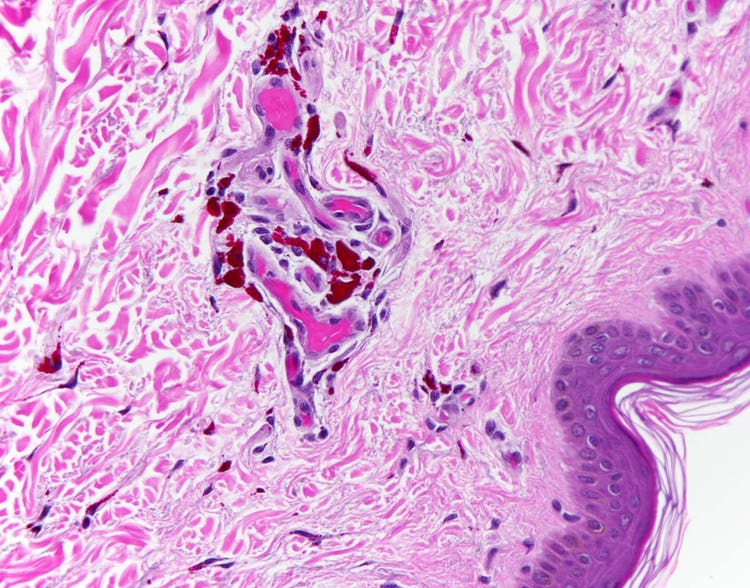

顕微鏡下で観察されるタトゥーの赤色色素

皮膚の切片にタトゥーが含まれている。高倍率により、個々の色素顆粒が皮膚の深層部である真皮で観察できる。顕微鏡下では他に黒色、青色、金色の色素顆粒が確認できる。オリンパスBX43顕微鏡とDP26カメラで撮影。画像提供: Marianne Hamel博士